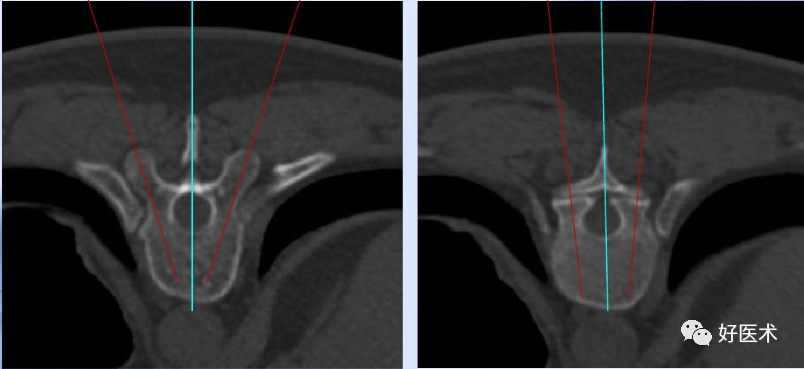

2.TSA、SSA:TSA角度可以从CT片子上测量,SSA与体位有一定关系,可以在术中用C型臂监控。

腰椎定向

胸腰交界向内倾斜5°

L2向内倾斜10°

L5向内倾斜15°

L1-4与终板平行

L5前倾10°